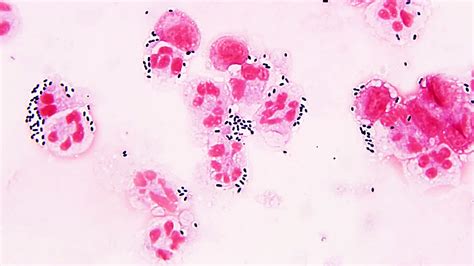

Alright, let’s start with the basics. Streptococcus pseudoporcinus is a type of bacteria that, while not super common, can cause infections in humans. Think of it like a less-famous cousin of other, more well-known Streptococcus bacteria. It’s often found in places like the skin and mucous membranes. The key thing to remember is that it’s an opportunistic pathogen, meaning it tends to cause problems when your body’s defenses are down, like if you’re already sick or have a weakened immune system. It can cause various infections, and it’s essential to understand the specific symptoms and how to get the right diagnosis and treatment. The most common infections are related to endocarditis, though it could impact other areas of the body.

Knowing the signs and getting a proper diagnosis are super important. The symptoms of a Streptococcus pseudoporcinus infection can vary depending on where the infection is located. Common symptoms include fever, chills, and fatigue. If the infection involves the heart (endocarditis), symptoms might include heart murmurs, shortness of breath, and chest pain. If you suspect you might have an infection, it’s essential to see a doctor right away. They’ll likely take a blood sample or a sample from the infected area to run some tests. To diagnose a Streptococcus pseudoporcinus infection, the doctor will often use a blood culture. This involves taking a blood sample and growing any bacteria present in a lab. The lab can then identify the specific type of bacteria causing the infection. Other tests, like an echocardiogram (an ultrasound of the heart), might be used to check for heart damage.